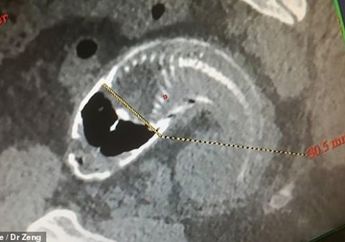

Mengerikan! Kesakitan saat Buang Air, Seekor Ikan Nila Ditemukan dalam Tubuh Pria Ini

5 Tahun yang lalu - Ikan nila yang diduga berukuran 30-40 sentimeter itu berada di dalam rektum, organ yang terletak di antara ujung bagian usus besar dan anus